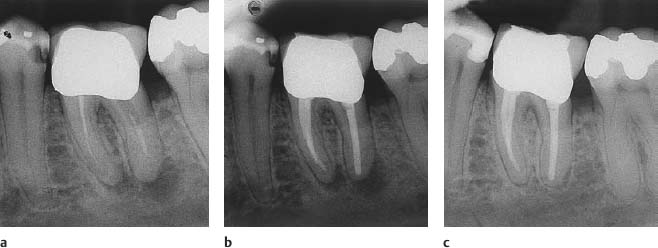

Рентгеновские снимки кариеса корня зуба

Раздел: Визуальные уроки